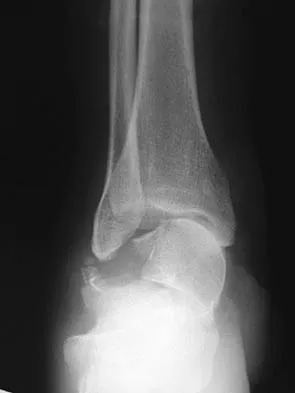

Figure 31 shows the AP and lateral radiographs of the elbow of a 56-year-old man with chronic polyarticular rheumatoid arthritis. His function continues to be limited by pain with activities of daily living. Examination shows that his total arc of motion is 110 degrees. Nonsurgical management has failed to provide relief. Treatment should now consist of

Explanation

A semiconstrained prosthesis can provide excellent results in carefully selected patients. Because the radiographs show extensive joint destruction with loss of the capitellum and trochlea, a capitellocondylar total elbow (unconstrained) prosthesis is contraindicated. Elbow fusion is poorly accepted, and the radiographs show too much articular destruction for a radial head excision, synovectomy, or interposition arthroplasty to be effective. Ewald FC, Simmons ED Jr, Sullivan JA, et al: Capitellocondylar total elbow replacement in rheumatoid arthritis: Long-term results. J Bone Joint Surg Am 1993;75:498-507.